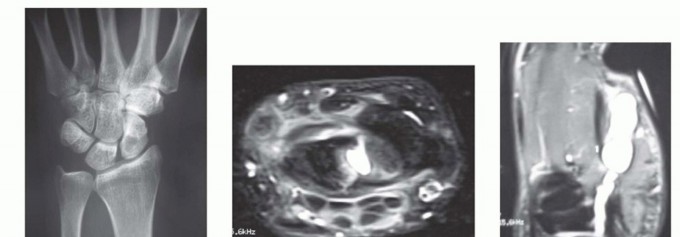

Accurate diagnosis relies heavily on a thorough history and physical examination. Transillumination is a simple, highly effective bedside test; ganglion cysts will brilliantly transilluminate, whereas solid tumors like GCTTS or keratin-filled EICs will not. Advanced imaging is not routinely required for classic presentations but is invaluable for atypical masses, recurrent lesions, or when preoperative planning requires precise mapping of neurovascular structures.

Clinical & Radiographic Imaging Archive